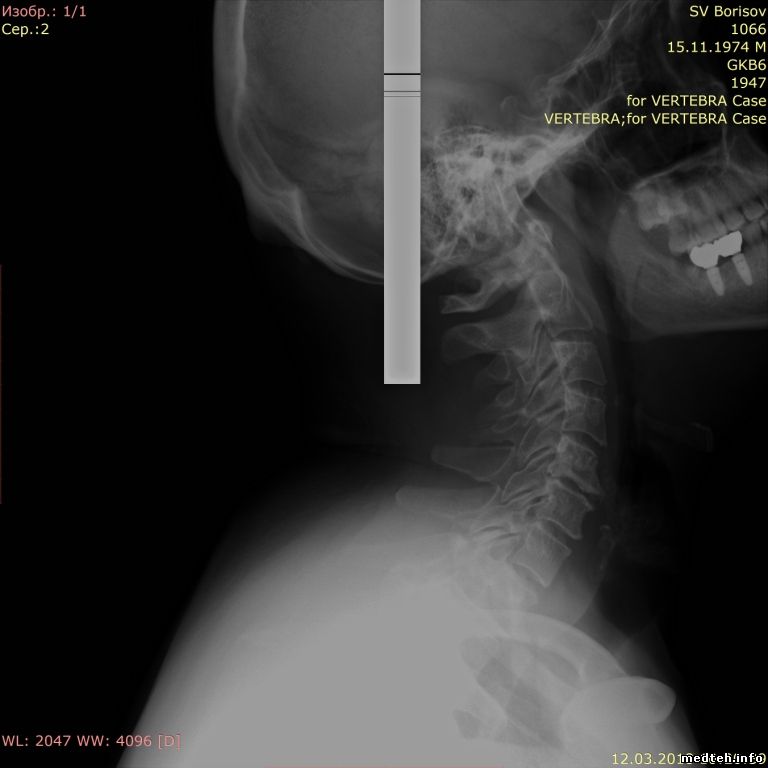

Может кто сталкивался-помогите советом, белая полоска на всех снимках. Пока был на гарантии, такая проблема появлялась, но была устранена переустановкой ПО (было до меня, что именно переустанавливали не ясно), после окончания гарантии тоже переустанавливали ПО - не помогло. Официалы не могут решить, сделали запросы в Германию и Японию, ждем уже месяц..

На всех режимах, кроме скопии - там нормально. Делал снимок на кассету от дигитайзера, там без артефакта.